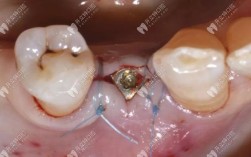

- 手术精准度:微创种牙借助CBCT(锥形束CT)、数字化导板等技术,可精准规划种植位置、角度和深度,避免损伤神经、血管,同时保证种植体周围骨均匀受力;

- 初期稳定性更高:数字化导板可实时调整种植方向,避免传统手术中因视野局限导致的偏差,尤其适合即刻种植(拔牙后立即植入),缩短拔牙-种植间隔,减少骨量流失;